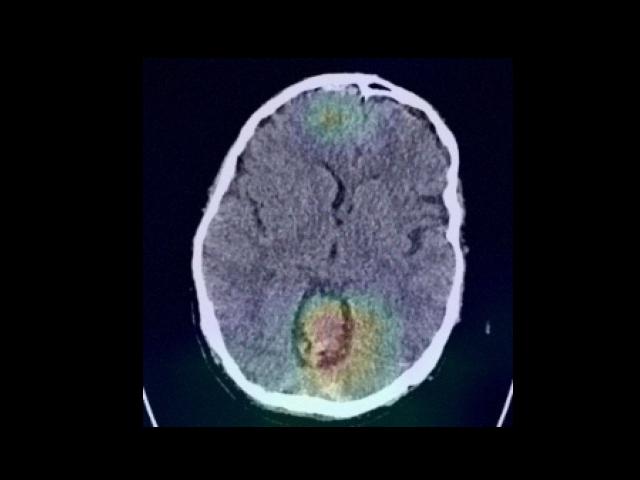

Sample Gallery